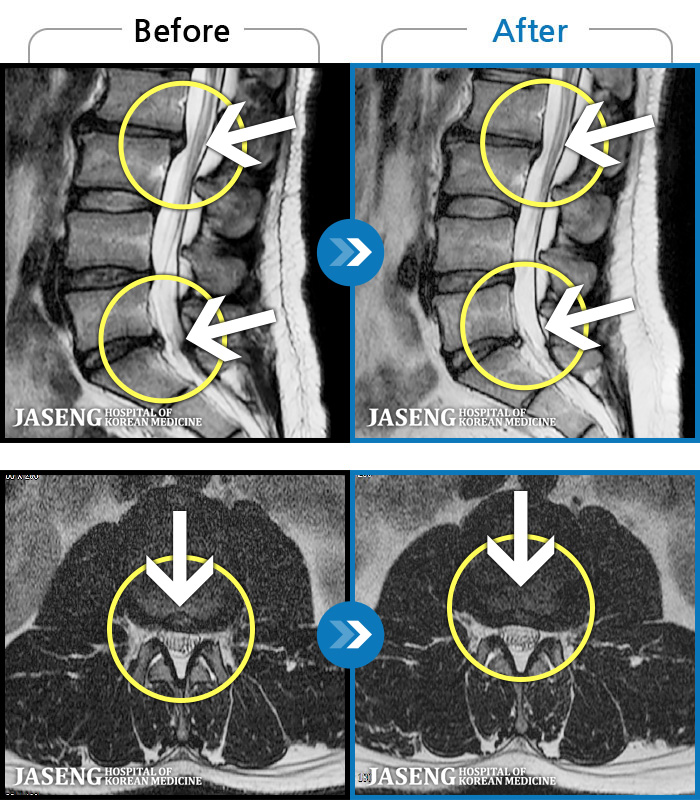

- MRI ġ

MRI ġ

1,237 MRI ũ ʸ Ȯϼ.